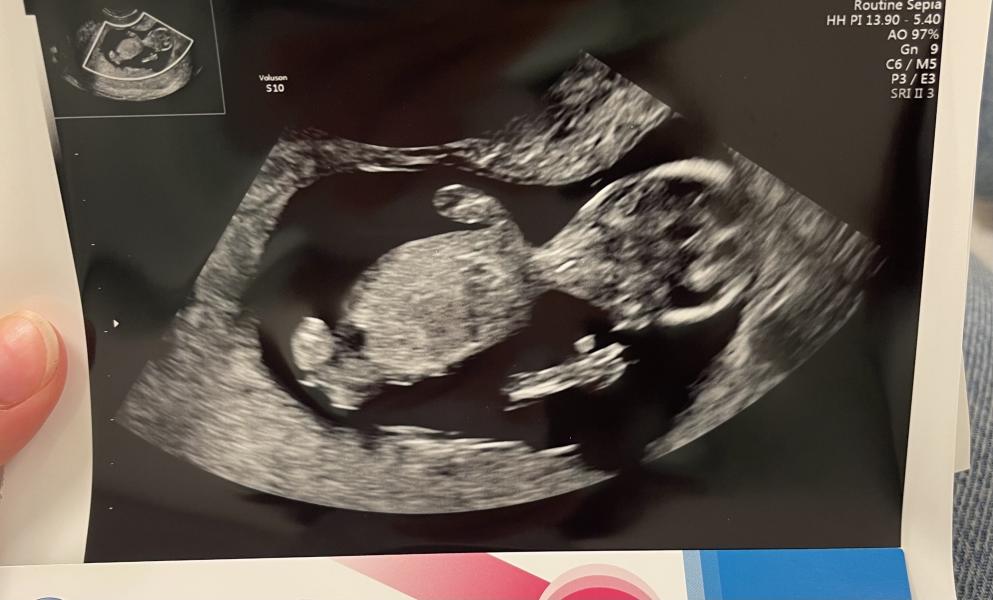

Первый триместр почти позади ☺️ Сегодня после скрининга мы открыли этот секретик родным.

На узи я расплакалась от избытка чувств, от того как этот малыш танцевал и кривлялся перед камерой🥰

Токсикоз был и есть но легче чем с Микой. Успела попасть в больницу под капельницы и тогда же первый раз увидела бусинку, тогда было 8 недель.